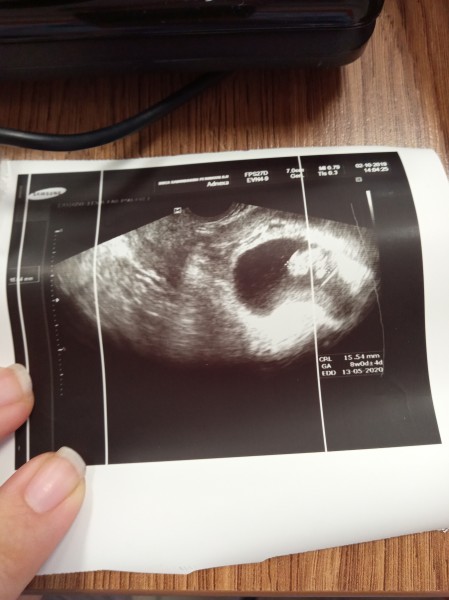

7+4 de doktor kese boş bebek yok ,bebeği besleyen damar kese bile yok demişti .Bugün tekrar gittim ne zaman kürtaj yaparlar acaba diye düşünerek gitmiştim ki bebeğimi gördük canlı ,sağlıklı çok şükür .Boş kese denen hamileler lütfen bekleyin hemen karar vermeyin.

Gebelik haftası 8+6